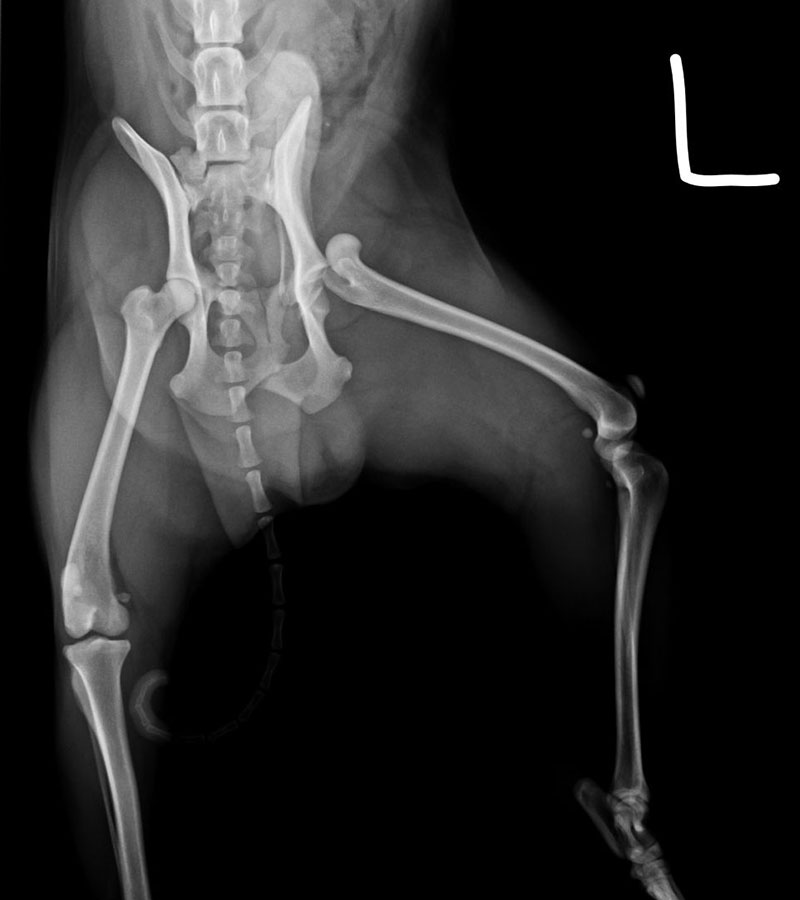

股骨頭脫位

車禍導致左後肢疼痛不敢踩地的柴弟經過X光確診為股骨頭脫位,跟飼主討論不同的治療方式後最後決定採用股骨頭切除術,目前已解除疼痛並回復正常行走。